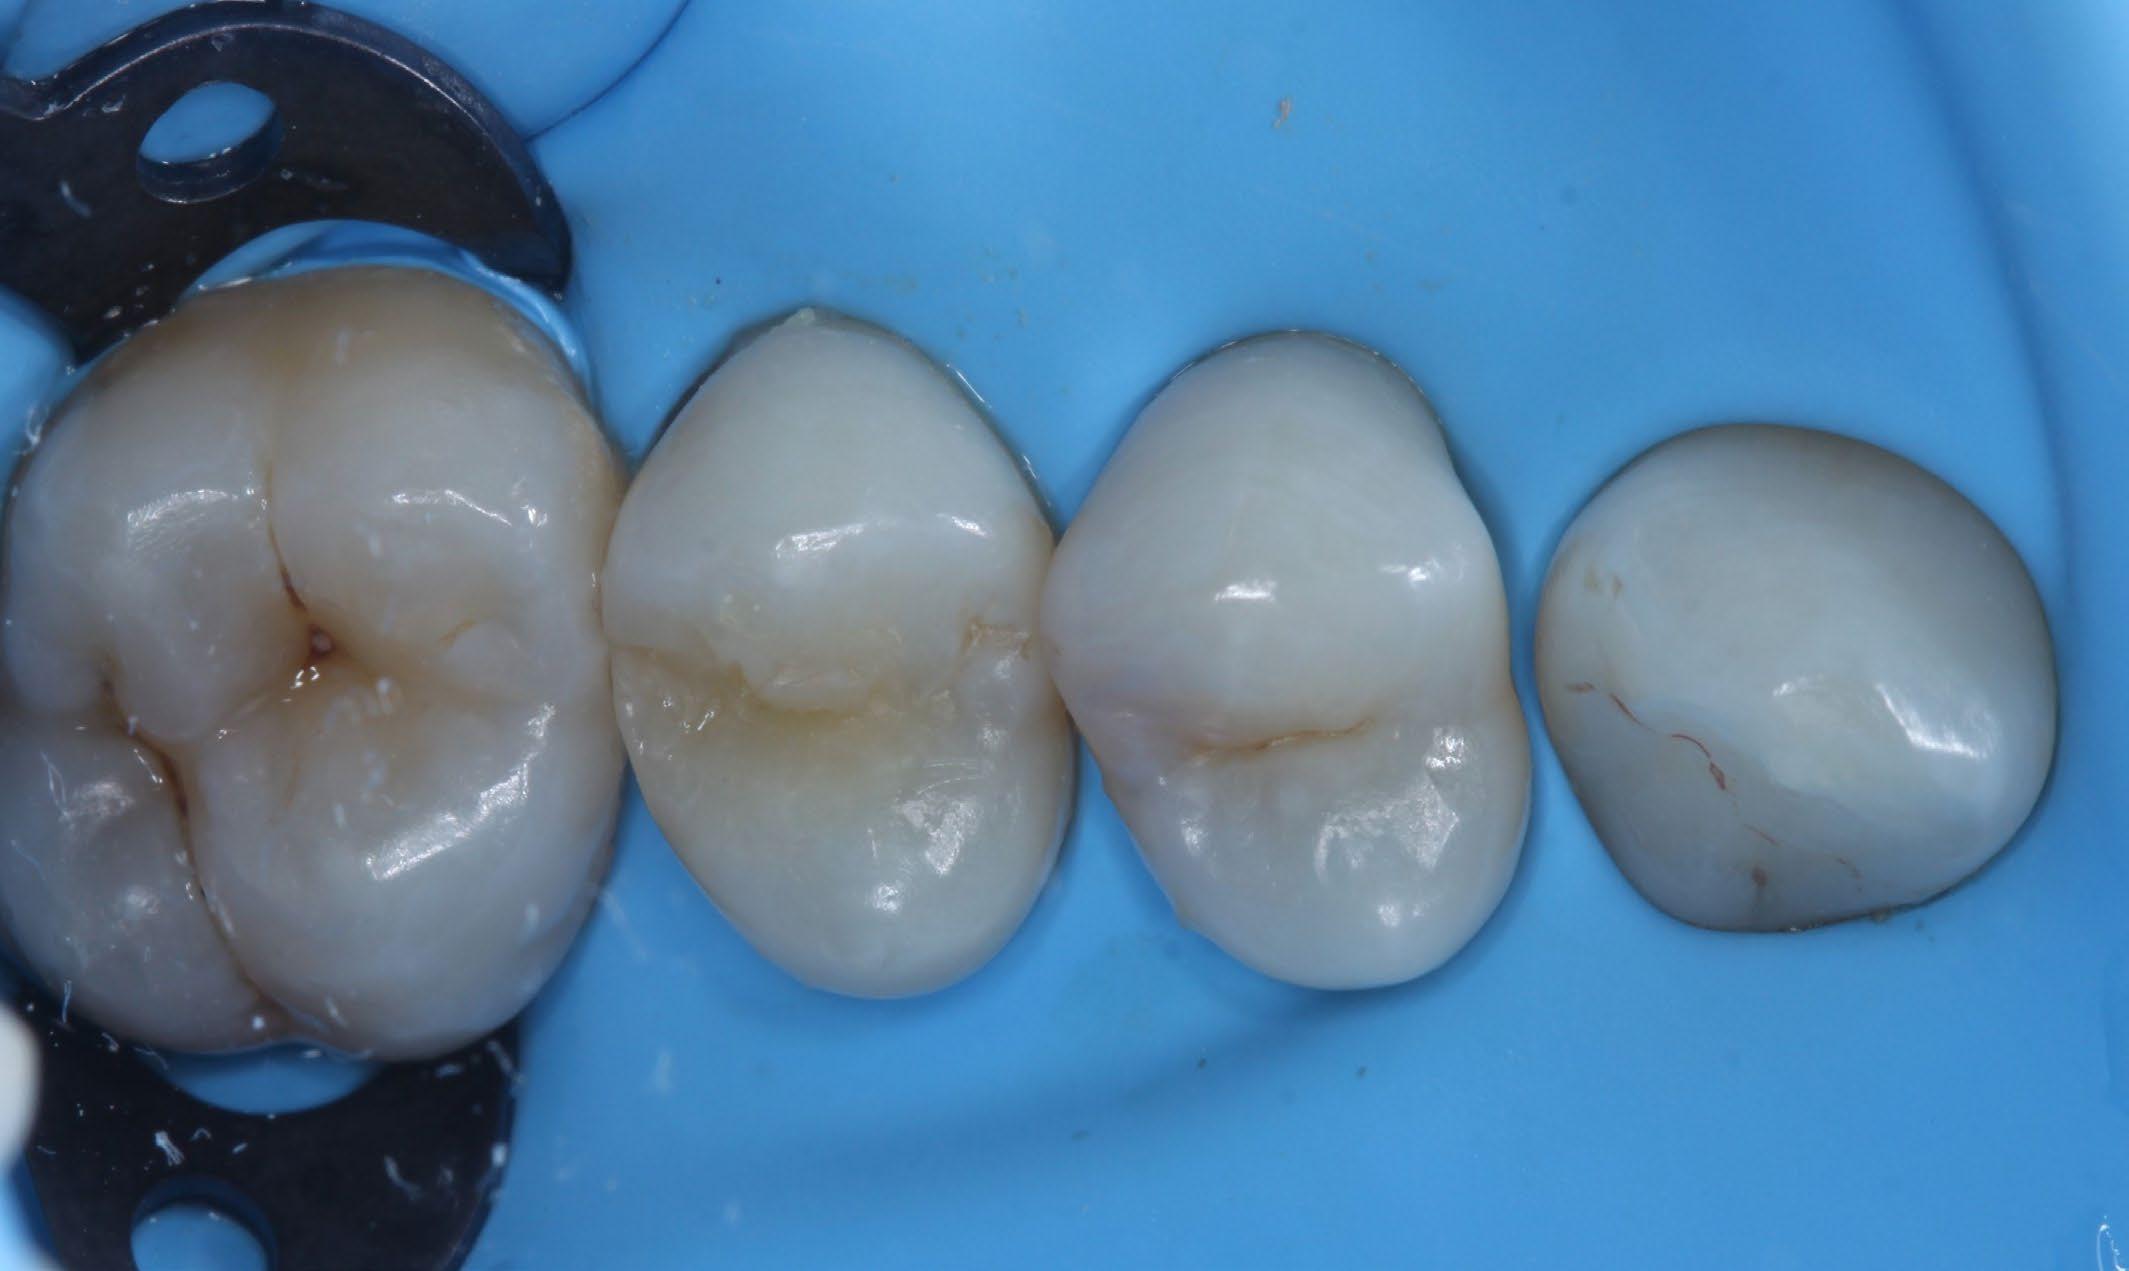

Fig. 9: The restoration was polished with the first spiral in the two-step 3M™ Sof-Lex™ Diamond Polishing System. Fig. 10: A high gloss was achieved using 3M™ Sof-Lex™ Diamond Polishing System’s second spiral. Fig. 11: Polished restoration. Fig. 12: Final restoration.